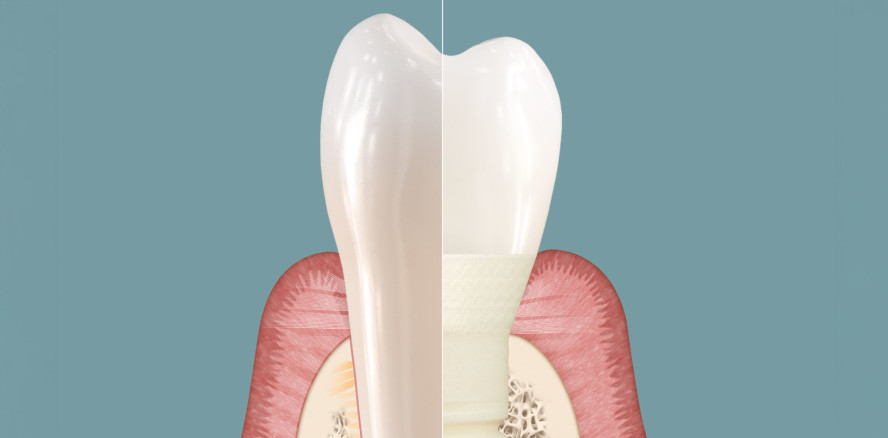

PATENT MEDICAL – Natürliche Zähne sind im Weichgewebsbereich von einer Schutzbarriere umgeben. Diese verhindert, dass Bakterien in das umliegende Gewebe eindringen. Geht ein Zahn verloren, wird auch dessen Schutzbarriere zerstört. Dentale Implantate sind heute nicht in der Lage, diesen Schutzmechanismus wiederherzustellen.

Mit Symbionic Teeth ist dies nun allerdings möglich.

Symbionic Teeth sind sie die konsequente Weiterentwicklung von dentalen Implantaten: Durch das Verwachsen mit oralem Weichgewebe erzeugen sie eine mukosale Schutzbarriere nach Vorbild des natürlichen Zahns. Dieser Vorgang wurde bei Symbionic Teeth der Marke Patent™ erstmals überhaupt für eine Zahnersatzlösung wissenschaftlich nachgewiesen.1-3

Die mukosale Schutzbarriere rund um Patent™ Symbionic Teeth schirmt das Gewebe vor Plaquemigration und oralen Krankheitserregern wie Bakterien ab. Dieser Durchbruch bietet Zahnersatzspezialisten erstmals die Möglichkeit, die Gewebegesundheit zu erhalten und die Risiken von Rezessionen und Knochenverlusten drastisch zu reduzieren.